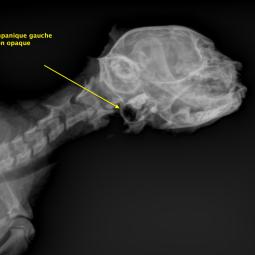

La trépanation de la bulle tympanique:

Cette technique chirurgicale consiste à perforer la paroi de la bulle tympanique et nettoyer son contenu. La chirurgie est nécessaire lors d'otite moyenne (accumulation de liquide dans la bulle tympanique) qui ne régresse pas avec un traitement médical.

Le diagnostic peut se faire par radiographie (cf images joints) mais l'examen de choix reste le scanner ou l'IRM si on souhaite une exploration fine de l'oreille interne.

A noter que les images présentes ici sont celles d'un chaton qui présente une otite moyenne droite modérée qui a été soignée à l'aide d'un traitement anti-inflammatoire et antibiotique.

Radio de profile pour l'exploration de la bule tympanique droite

Radio de profile pour l'exploration de la bule tympanique gauche